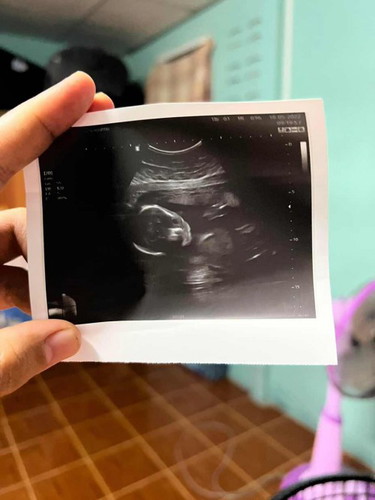

อยากรู้ขนาดศรีษะน้อง

ขอดูใบซาวด์ของ น้อง20wหน่อยได้มั้ยคะ มีแต่คนบอกของแม่บ้านนี้ มีผู้ใหญ่บอกเหมือนน้องจะหัวใหญ่ แต่คุณหมอก็ว่าปกติเพราะขนาดศรีษะของน้องปกติดี ตอนนี้แม่ก็กังวลกับคำพูดคนรอบข้างมากเลยค่ะ

บ้านนี้ครบ22สัปดาห์เมื่อวันที่14มิถุนาที่ผ่านมาค่ะ EFWน้ำหนักทารก=543g EPDวัดความกว้างศีรษะทารก=5.20 ACวัดเส้นรอบท้องทารก=18.12 FLวัดกระดูกต้นขาทารก=4.05 ใบซาว์ดเราประมาณนี้ค่ะแม่ คุณหมอไม่ได้แจ้งอะไรเพิ่มเติม คิดว่าไม่มีอะไรน่ากังวลค่ะ

มุมซ้ายจะมีตัวหนังสืออยู่ ขนาดรอบหัวจะเขียนว่า HC : แล้วแม่ดูหลังตัวเลขว่าได้กี่วีค ถ้าไม่มากกว่าอายุครรภ์จริงเกินไปมาก ๆ ถือว่าปกติค่ะ

ในรูปดูไม่ออกหรอกค่ะ หมอวัดจากเครื่องอัลตราซาวน์ ถ้าจากสายตาวัดได้ ฝากครรภ์คงไม่ต้องไปแล้วค่ะ

คนรอบข้างไม่ได้เป็นหมอค่ะแม่ 20 w น้องยังโตไม่เต็มที่เลย ร่างกายยังพัฒนาได้อีกจ้า รูปนี้ตอน 21 w 5 d

ในใบก็จะมองเป็นหัวใหญ่ปกติค่ะแม่ ถ้าหมอวัดแล้วปกติก็คือปกติอย่าคิดมากนะคะ